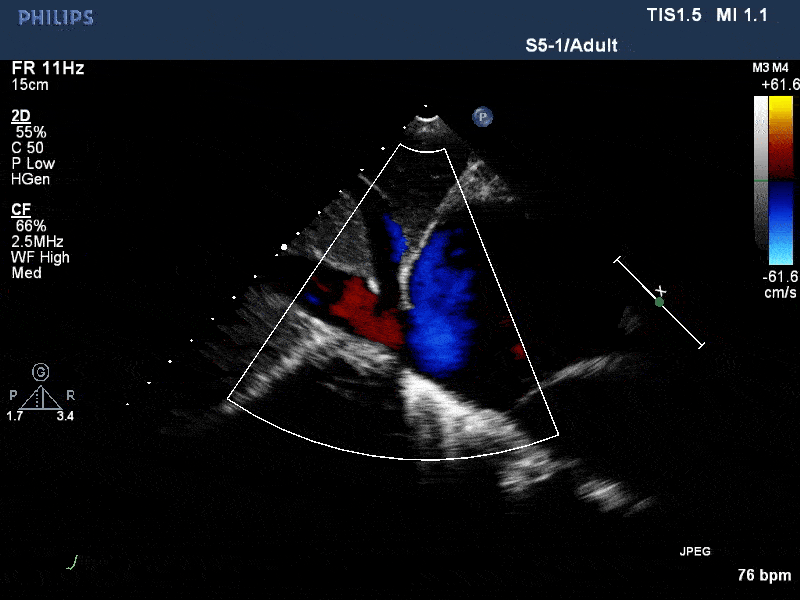

术前与术后30天门静脉反流比较

术前超声:肝门静脉重度反流